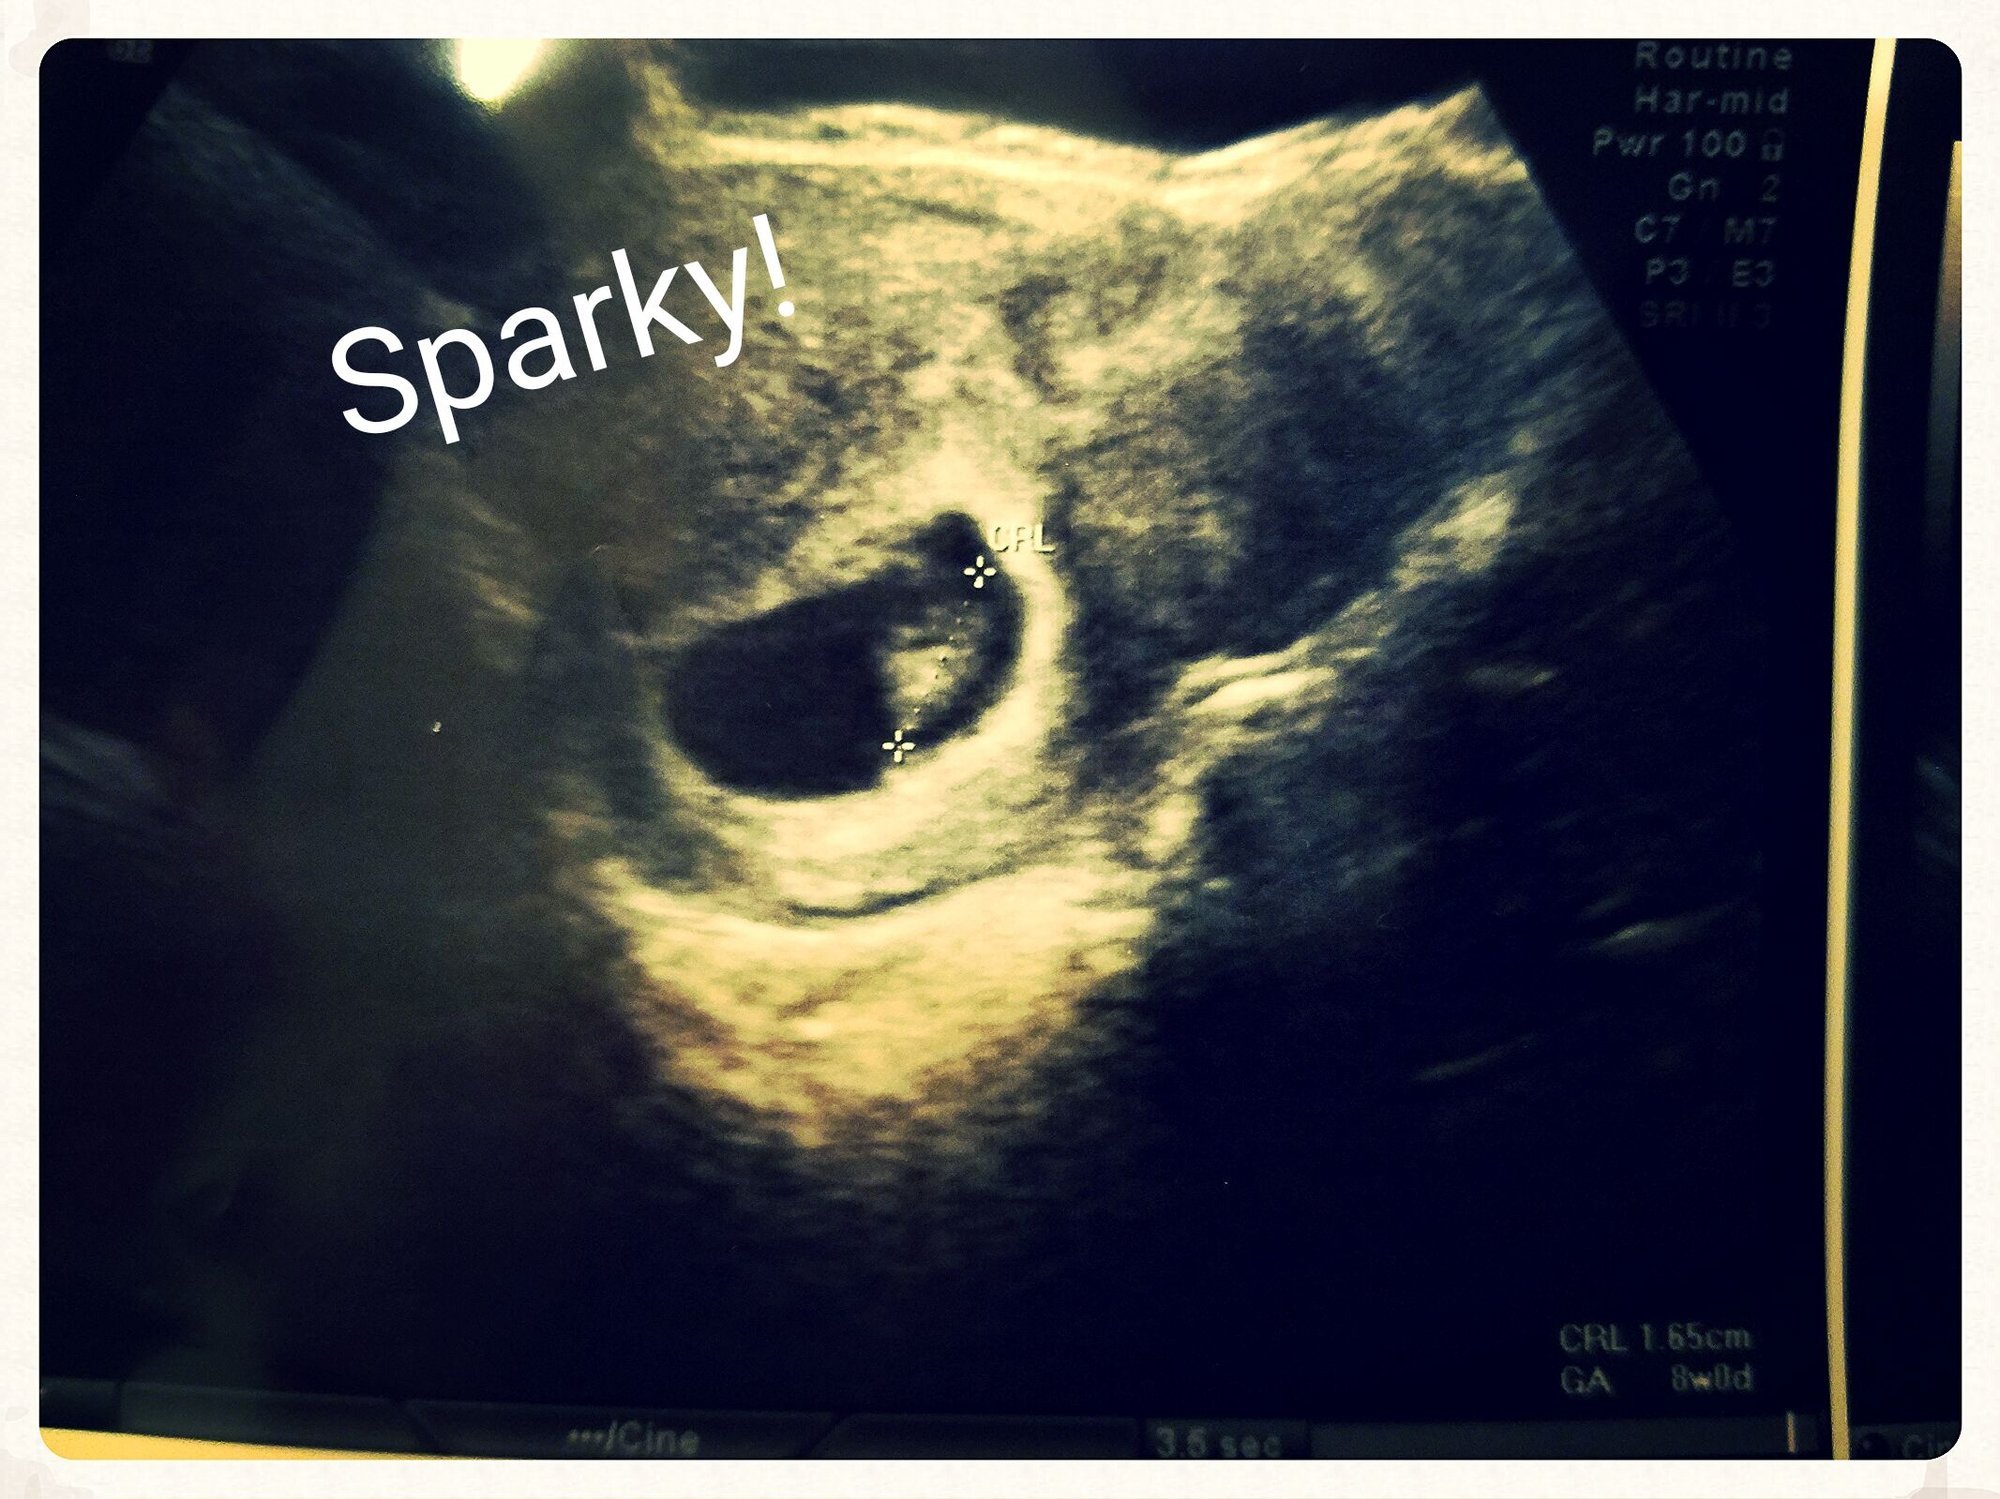

Our little nugget! Based off of LMP I should be 6w3d but only measured 5w6d and HB was 115bpm. I'm a little worried because I had a miscarriage with my first pregnancy that was 4 days behind and around the same HB.